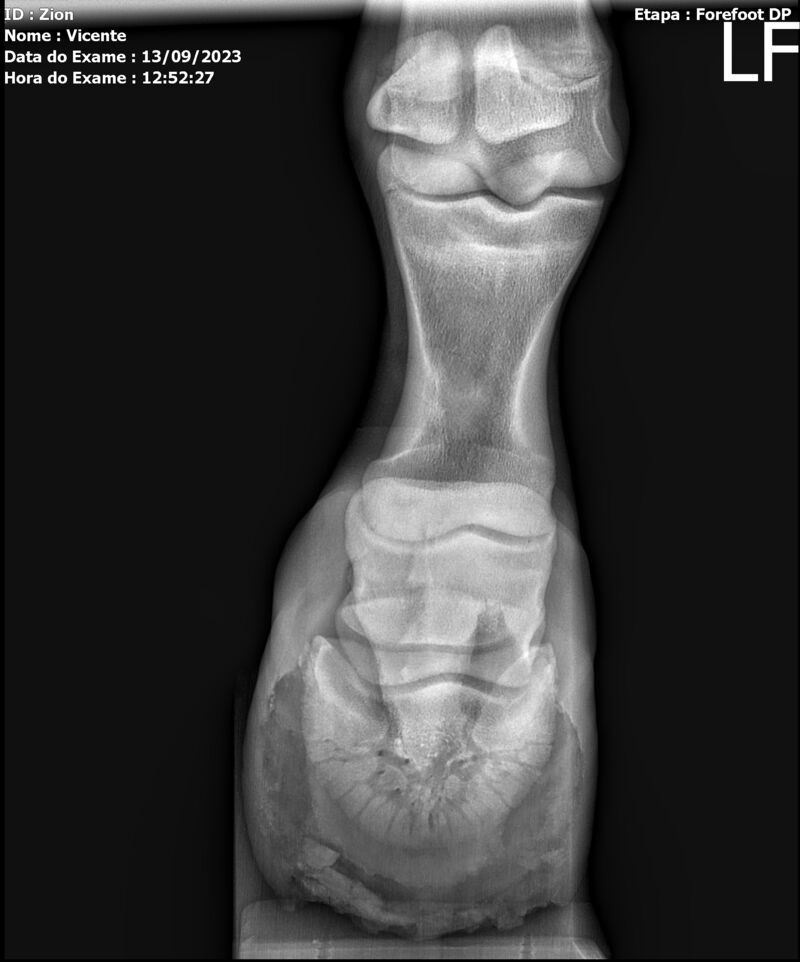

ZION ZC

Raça: BRASILEIRO DE HIPISMO

Sexo: MACHO - POTRO

Nascimento: 17/12/2022

Altura Aproximada: 1,51

Pel.: CASTANHO

Registro: EM AND

Vend.: VICENTE CONTE

Local : PORTO FELIZ/SP